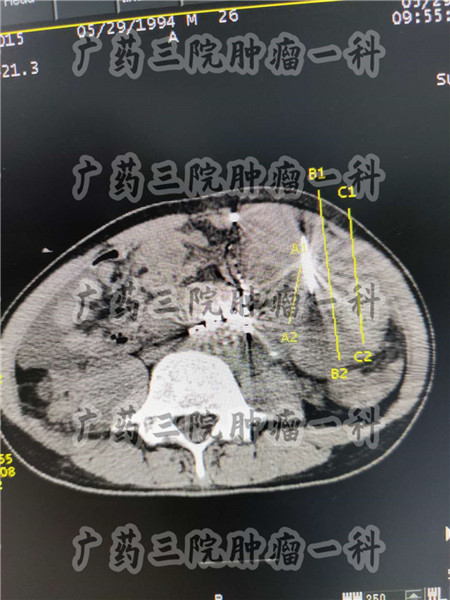

而不能手术治疗的直肠癌患者也不少见,广药三院肿瘤科一区有的直肠癌患者,此前经胃肠外科会诊后考虑直肠肿瘤后壁与骶尾部固定不可推动,手术难以完整切除,因此医生不建议进行手术治疗。

在广药三院肿瘤科一区,彭齐荣教授建议患者进行微创治疗,一方面,对不愿意手术,或已经不能手术切除的直肠癌患者来说,微创手术的创伤小,不会让患者元气大伤,患者术后恢复也比较快。尤其是患者如果经过会诊讨论,适合血管靶向治疗的话,那么患者手术后,只需要卧床6小时,就能下地走动了。

直肠癌患者选择微创治疗,可以根据病情选择合适的治疗方案。肿瘤的微创治疗技术有很多中,其中粒子治疗、靶向治疗、血管灌注、血管栓塞、光动力治疗等等,都能针对肿瘤进行局部精准治疗,广药三院肿瘤科一区医生联合中医治疗、影像学科等多学科联合会诊,将肿瘤局部精准治疗与全身免疫防复发治疗相结合,为患者制定合适的治疗方案。